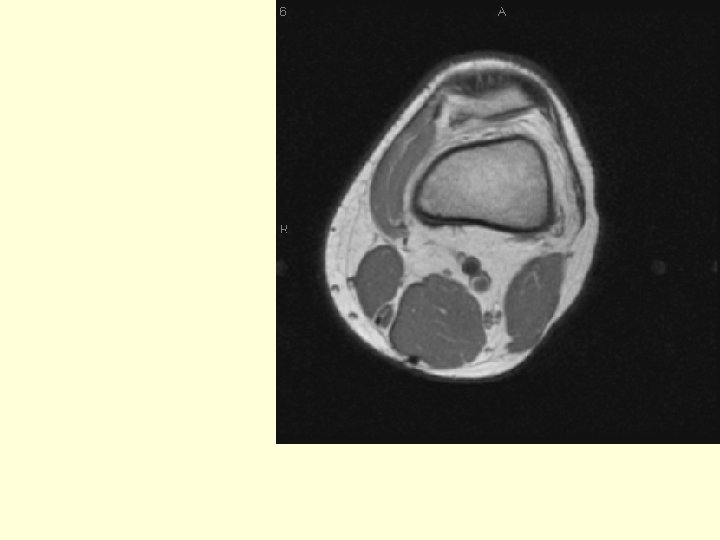

Note how the muscles change around the knee. The semitendinosis and the gracilis are just tendons (black dots) at this level. Semitendinosis Gracilis